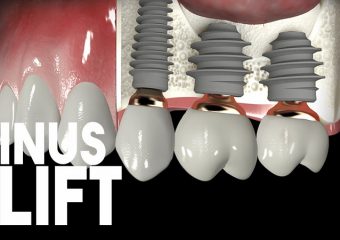

سینوس لیفت چیست؟

عمل سینوس لیفت

سینوس لیفت چیست؟

سینوس لیفت یا همان تقویت سینوس، جراحی است که جاگذاری ایمپلنتهای دندان را آسانتر میکند. برخی از افراد به ایمپلنت دندان احتیاج دارند اما به دلیل از دست دادن استخوان، پشتیبانی کافی از استخوان که برای ایمپلنت لازم است را ندارند. این عمل میتواند در این زمینه کمک کند زیرا با افزودن استخوان به فضای بین دندانهای مولار و پرمولار، میزان استخوان در فک بالا را افزایش میدهد. جهت ایجاد فضا برای استخوان، غشای سینوس باید به سمت بالا حرکت داده شود و یا “بلند شود”، به همین دلیل این جراحی سینوس لیفت نامیده میشود. یک متخصص ایمپلنت مانند جراح فک و صورت یا پریودنتیست معمولاً لیفتهای سینوس را انجام میدهد.